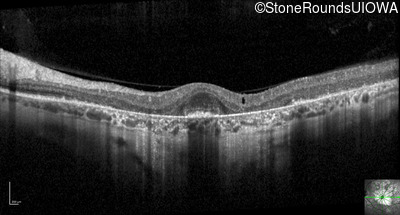

Optical Coherence Tomography - Right - 20/32 +2

Exemplar / OCT Stack

OCT Stack